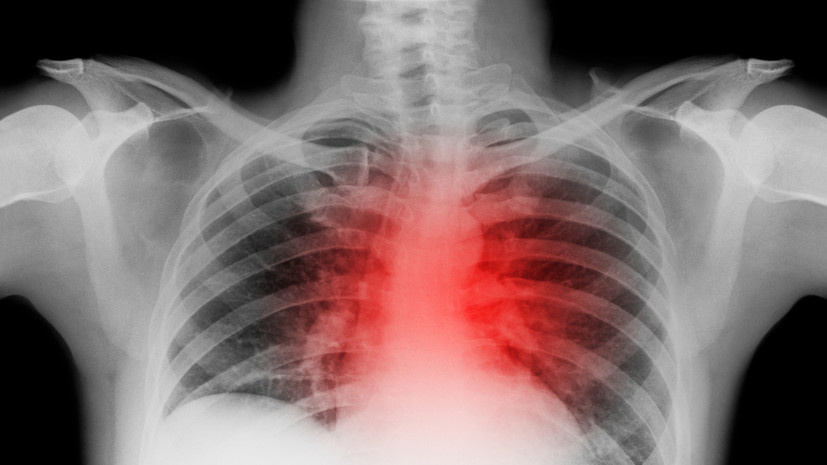

Врачи городской больницы Асбеста спасли 56-летнего жителя Сухого Лога с редким осложнением инфаркта миокарда, рассказали в Департаменте информационной политики Свердловской области. Об этом сообщает URA.RU. «Мужчина был доставлен в больницу на скорой помощи в критическом состоянии с пульсом всего 30 ударов в минуту. Ему был поставлен диагноз «инфаркт миокарда». Срочно была выполнена операция по стентированию сосудов сердца, а также установлен кардиостимулятор», — говорится в сообщении. После операции мужчину перевели в реанимацию, где у него развилось новое осложнение — его пульс резко увеличился. В течение этого периода сердце пациента останавливалось семь раз, и каждый раз медики спасали ему жизнь. Мужчине выписали антиаритмические препараты, его состояние улучшилось. Ранее «Радио 1» сообщало, что подмосковные врачи спасли четырёхмесячного ребёнка с энцефалитом.